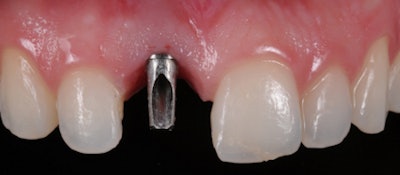

The following patient was an excellent candidate for a single-tooth implant. The patient was 35 years old when she lost her upper right central incisor (No. 8) because of a traumatic injury.

She had adequate bone and healthy gum tissue, and the adjacent teeth were in good condition. While placing a bridge would have required altering teeth Nos. 7 and 9, an implant was placed to support a single crown. By doing so, the adjacent teeth were preserved, and the patient was able to eat, talk, and smile with confidence.

We have every reason to expect this implant to be in service throughout her life. Later in life, if her gums recede with age, some aesthetic touch-up may be required at the cervical margins.